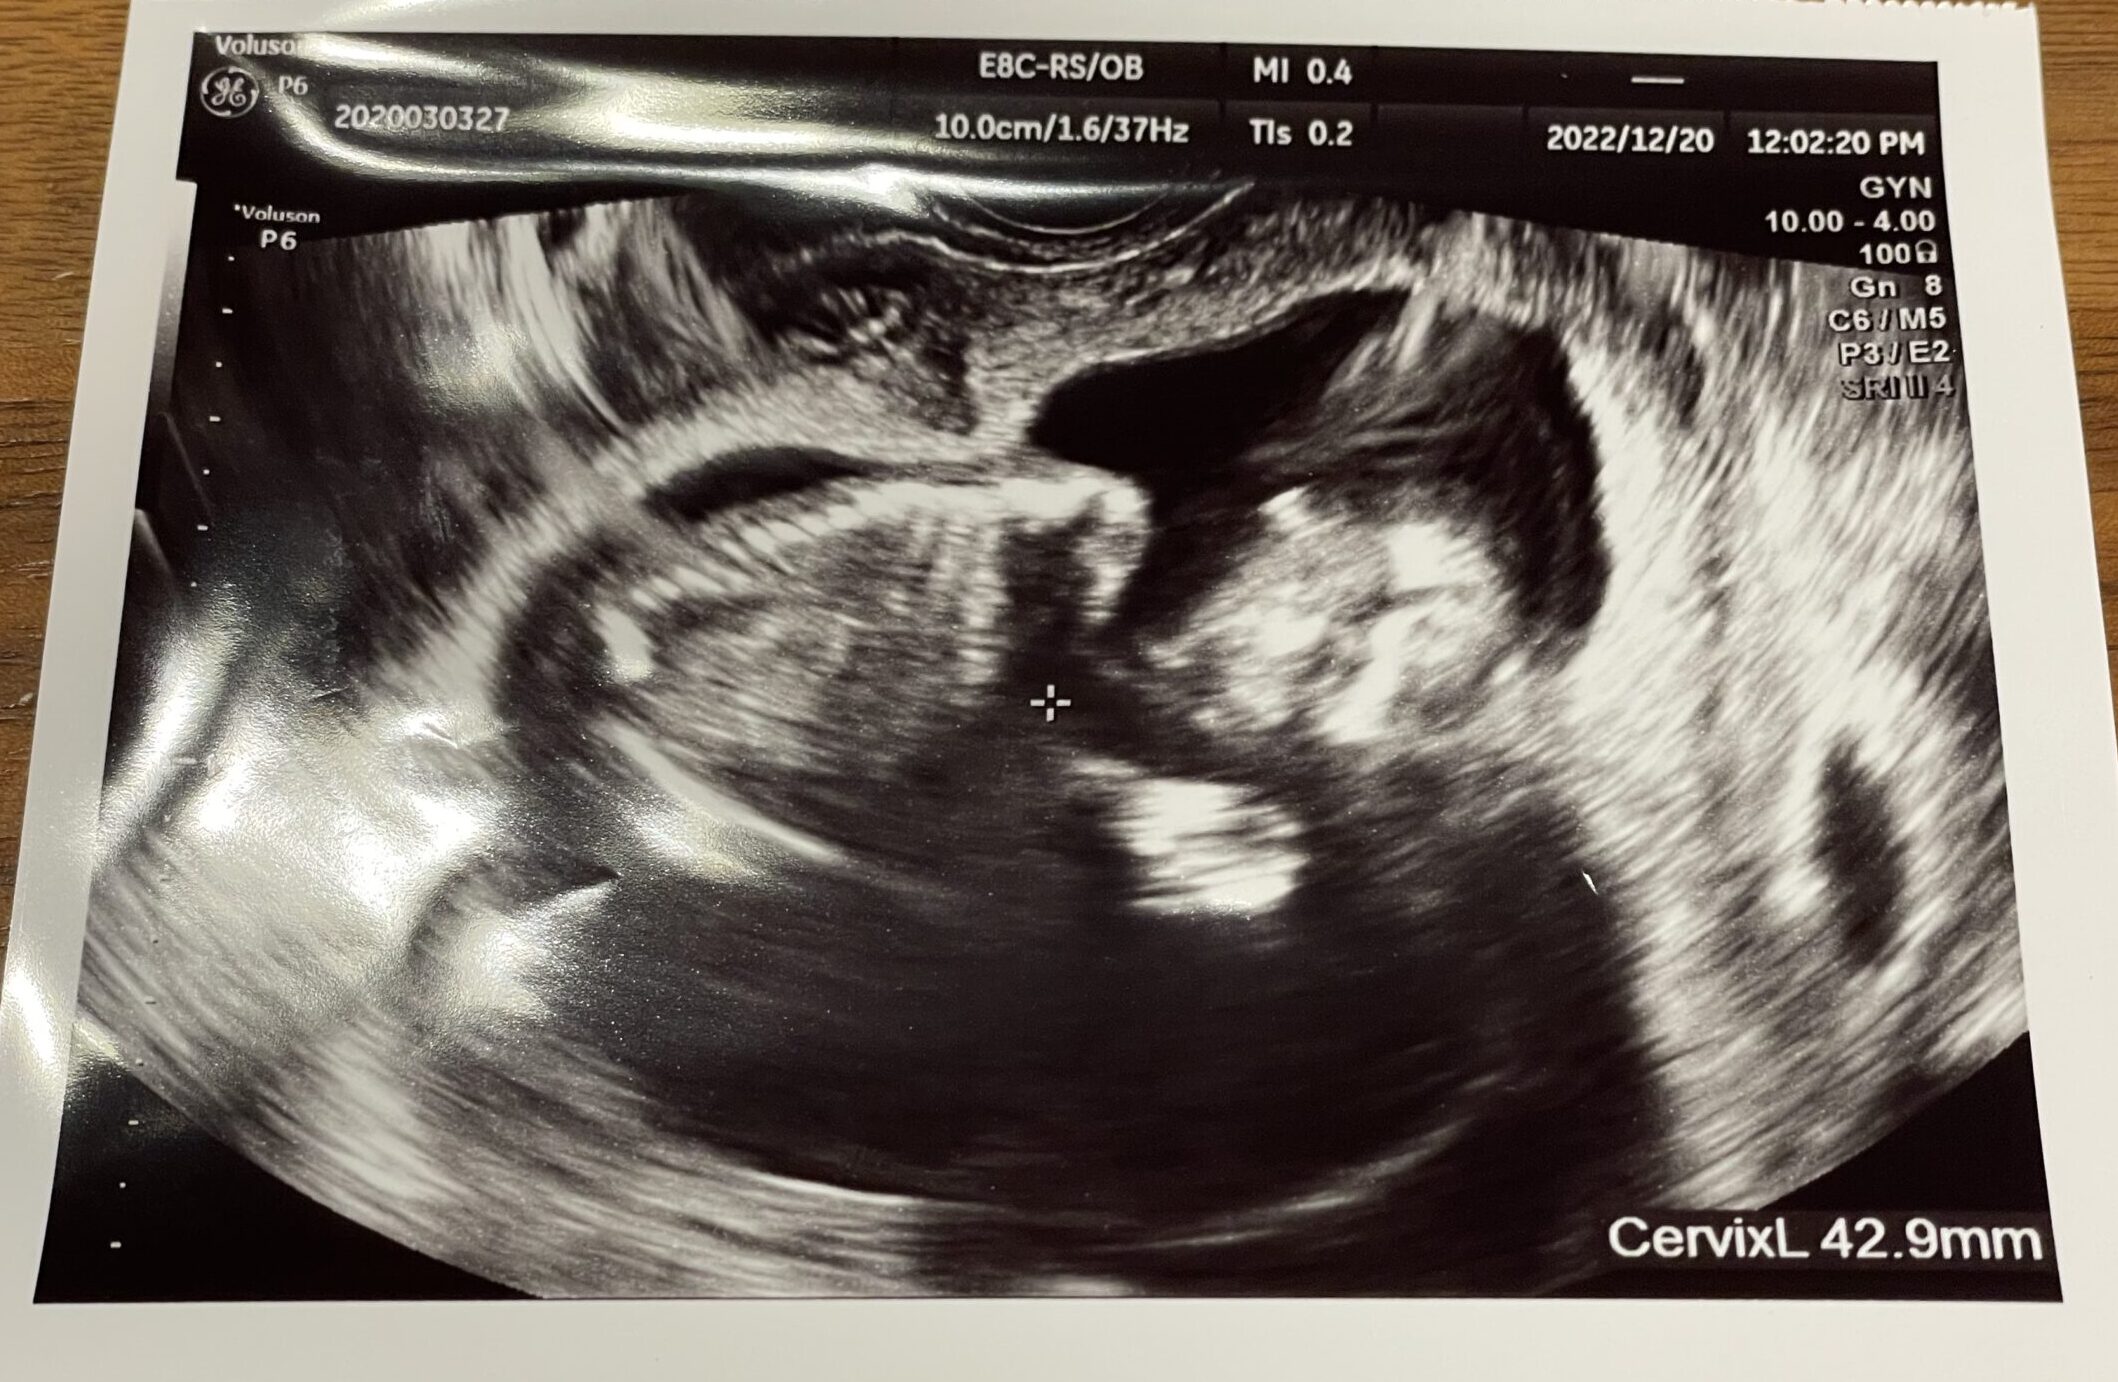

今回のエコー写真は、左頬を下にして寝そべっているような体制の赤ちゃんの姿が見られました。安心して泣きそうになりました(T_T)

今回は移動前ということで経膣エコーのみの健診となりました。

今回は体調不良をお起こした後のこともあったので、経膣エコーの不快感よりも「赤ちゃんに何かあったらどうしよう」という緊張感の方が勝っていました。

結果的には、お医者さんから異常についての言及は特になく、今の時点では大丈夫そうでした。